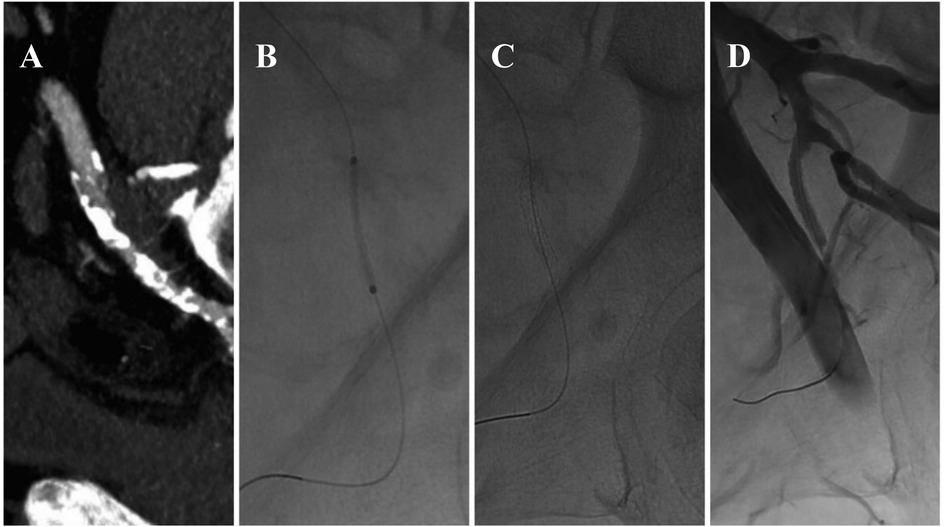

A Narrative Review of Endovascular Treatment in Addressing Arterial and Venous Erectile Dysfunction

Erectile dysfunction (ED) is a worldwide health concern and clinical condition for men, leading to high medical costs and imposing significant emotional and psychological burdens on sufferers annually. ED is associated with multiple causes, including psychological factors and organic issues such as arterial insufficiency and venous leakage. Endovascular treatments have emerged as promising options for managing ED, offering minimally invasive procedures that can improve blood flow to the penis and restore erectile function. Different endovascular interventional approaches have been implemented with varying success rates and therapeutic impacts, and efforts continue to optimize these methods (both arterial and venous) for maximum effectiveness and minimal invasiveness. This narrative review aims to provide an overview of endovascular treatments for arterial and venous types of ED, discussing their mechanisms of action, efficacy, safety, and future directions.